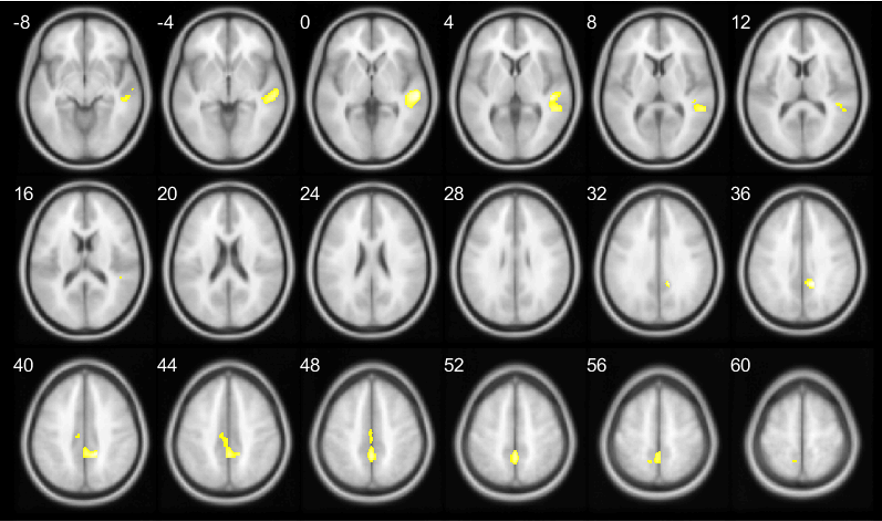

Results: The median time to cognitive impairment onset was significantly shorter in the OH group (70.7 months) compared to the non-OH group (92.4 months; p=0.006). Cox regression analysis revealed that OH was a significant predictor of cognitive impairment (HR=2.11, p=0.008). At baseline, the OH group exhibited reduced GMV in the precentral gyrus and superior temporal gyrus. During follow-up, these patients showed further GMV reductions in the inferior frontal gyrus and inferior occipital gyrus, suggesting that OH may contribute to cognitive decline through structural changes in specific brain regions.

Figure 1